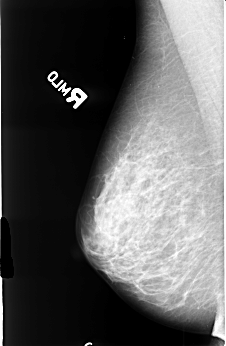

B_3477_1.RIGHT_CC

RIGHT_CC LINES 4464 PIXELS_PER_LINE 2936 BITS_PER_PIXEL 12 RESOLUTION 50 NON_OVERLAY